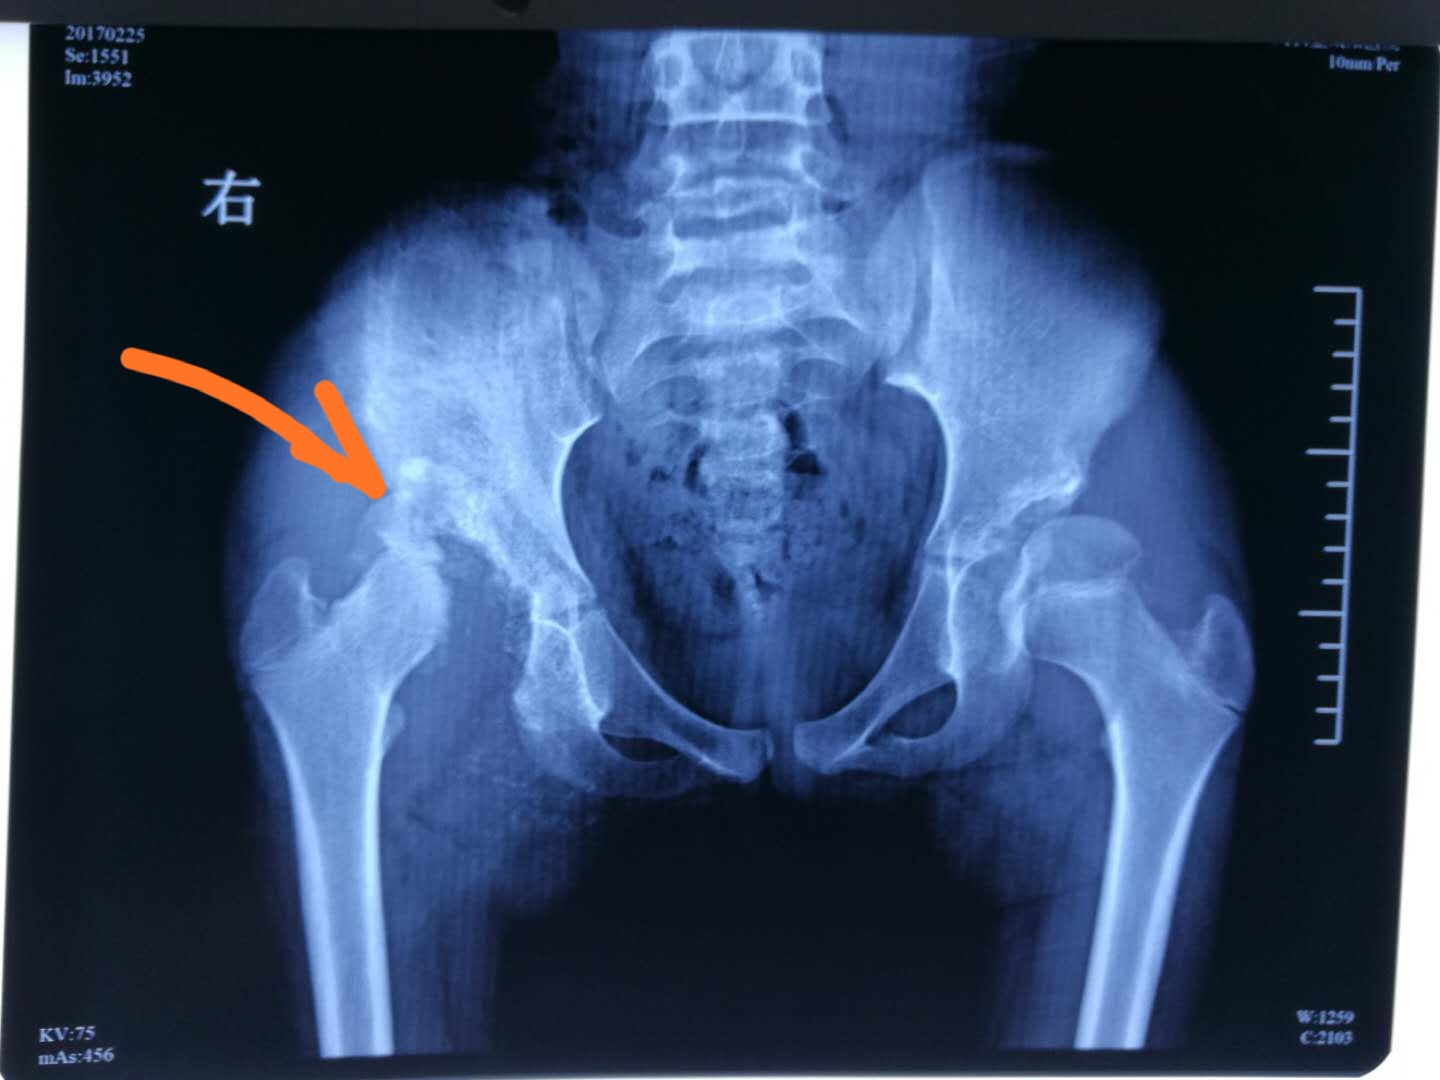

4年前,一位11岁的小女孩由她的母亲陪伴着来到我的门诊,孩子自幼打预防针时从来不哭,那时候乡里医生说孩子得了“怪病”,但不知道是什么“病”?不仅如此,炎热的夏天她也不会出汗,运动后脸部就会变红。但近来,孩子步态开始不正常,一次不经意地摔倒,感觉到手臂、脚踝肿了,拍片发现竟然腕部和小腿的骨头断了,让人不可思议的是孩子一点也不感觉到痛,照样走路!家人愈加担心了。我让孩子拍了骨盆和四肢的X光片子,让我大吃一惊:孩子的右侧股骨头已经被磨掉近一半了,医生心疼地询问孩子是否疼痛时,孩子竟然回答不痛!了解到孩子还有一个哥哥,但哥哥完全是正常人,家族中也没有类似的遗传病史。

11岁时拍片显示,右侧股骨头被磨掉二分之一